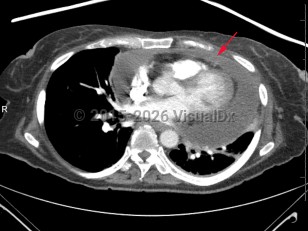

Cardiac tamponade is a true life-threatening medical emergency that is fortunately treatable with prompt diagnosis and treatment. Tamponade is a form of obstructive shock caused by elevated intrapericardial pressure that results in decreased cardiac filling and subsequent decreased cardiac output. Normally, the pericardium lacks compliance, and thus even a small increase in pericardial fluid can cause a rapid rise in pericardial pressure. If the pressure rises higher than the right-sided cardiac pressure, it causes decreased cardiac filling, ventricular interdependence, obstructive shock, and if untreated, cardiac arrest.

When intrapericardial pressure rises, it may yield in reduced cardiac filling secondary to changes in the right atrial-to-systemic venous pressure gradient. In severe cases, cardiac output is reduced to such an extent that the body is unable to maintain adequate systemic and coronary artery perfusion. Untreated, this leads to cardiovascular collapse and death.